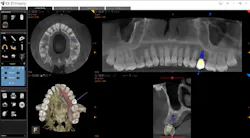

Whether it is an implant consultation for a single implant (figure 4), multiple implants, or full-mouth reconstruction, advanced 3-D software, such as the CS 3D Imaging software, offers you the ability to virtually plan the implant placement in regard to bone height, width, and density with respect to anatomical structures. Once planned, this information is reviewed with the patient in a clear and concise way that is easily understood (figure 5). In my experience, patients often state that they didn’t know that this type of technology was even possible within a dental office. Because of these reasons and more, I have found that case acceptance has gone up exponentially.

Figure 4: Planning an implant in CBCT software

There is no doubt in my mind that the incorporation of CBCT into your practice improves your patient care because it allows you to see a vast array of anatomical structures and conditions that may have been previously overlooked. With only a 2-D image of an area—whether it is for an endodontic procedure, removal of wisdom teeth, or placement of an implant—you are somewhat limited. However, with CBCT you can accurately identify an accessary canal in a tooth before to a root canal, a rotation of an impacted tooth prior to extraction, or pathology in a particular segment of bone.

Figure 5: Virtual planning of immediate implant placement